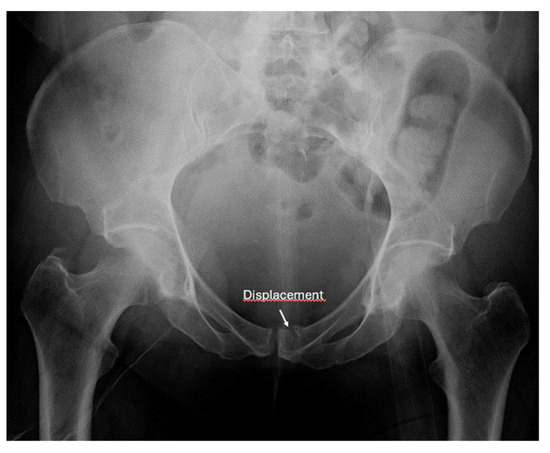

- Screening for fractures and hematoma during the primary survey in Advanced Trauma Life Support (ATLS), particularly in polytrauma patients, ultrasound enables rapid identification of fractures that are associated with life-threatening hemorrhage (e.g., pelvic or femoral fractures).

- Detection of instability signs in pelvic and spinal fractures: this is an emerging application where ultrasound can be used to assess dynamic instability or progressive displacement of fractures.

- Screening of fractures in the primary ATLS (Advanced Trauma Life Support) survey that are associated with or may cause life-threatening bleeding in polytrauma

- Recommendation 4: The E-FAST protocol, indicated for severely injured patients in shock, should be expanded to include fracture screening of long tubular bones and open-book fractures when the torso scan is negative for free fluid. This could identify hidden injuries and bleeding.

- Screening for instability in pelvic and spine fractures

- Ianniello, S.; Conte, P.; Di Serafino, M.; Miele, V.; Trinci, M.; Vallone, G.; Galluzzo, M. Diagnostic accuracy of pubic symphysis ultrasound in the detection of un-stable pelvis in polytrauma patients during e-FAST: The value of FAST-PLUS protocol. A preliminary experience. J. Ultrasound 2021, 24, 423–428. [Google Scholar] [CrossRef]

- Zhang, B.-F.; Lei, J.-L.; Zhang, H.; Wang, P.-F.; Wang, H.; Cong, Y.-X.; Huang, H.; Zhuang, Y. Use of ultrasonography for evaluation of stability of lateral compression type 1 (LC-1) pelvic fractures to assist determination of treatment strategy. J. Orthop. Surg. Res. 2019, 14, 7. [Google Scholar] [CrossRef]

- Zhang, B.-F.; Zhang, H.; Wang, P.-F.; Wang, H.; Lei, J.-L.; Fu, Y.-H.; Cong, Y.-X.; Huang, H.; Huo, X.-M.; Zhuang, Y.; et al. The role of ultrasonography in examination of the stability of Tile-B2 pelvic fractures: 7 case reports and a literature review. Med. (Baltim.) 2017, 96, e8100. [Google Scholar] [CrossRef]